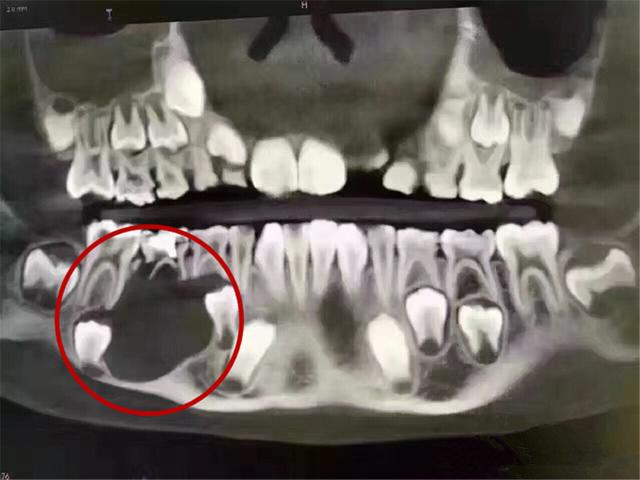

這是一位9歲的孩子,因為(wei) 沒有重視乳牙護理和齲齒治療,導致乳牙下麵的頜骨大麵積吸收的**。